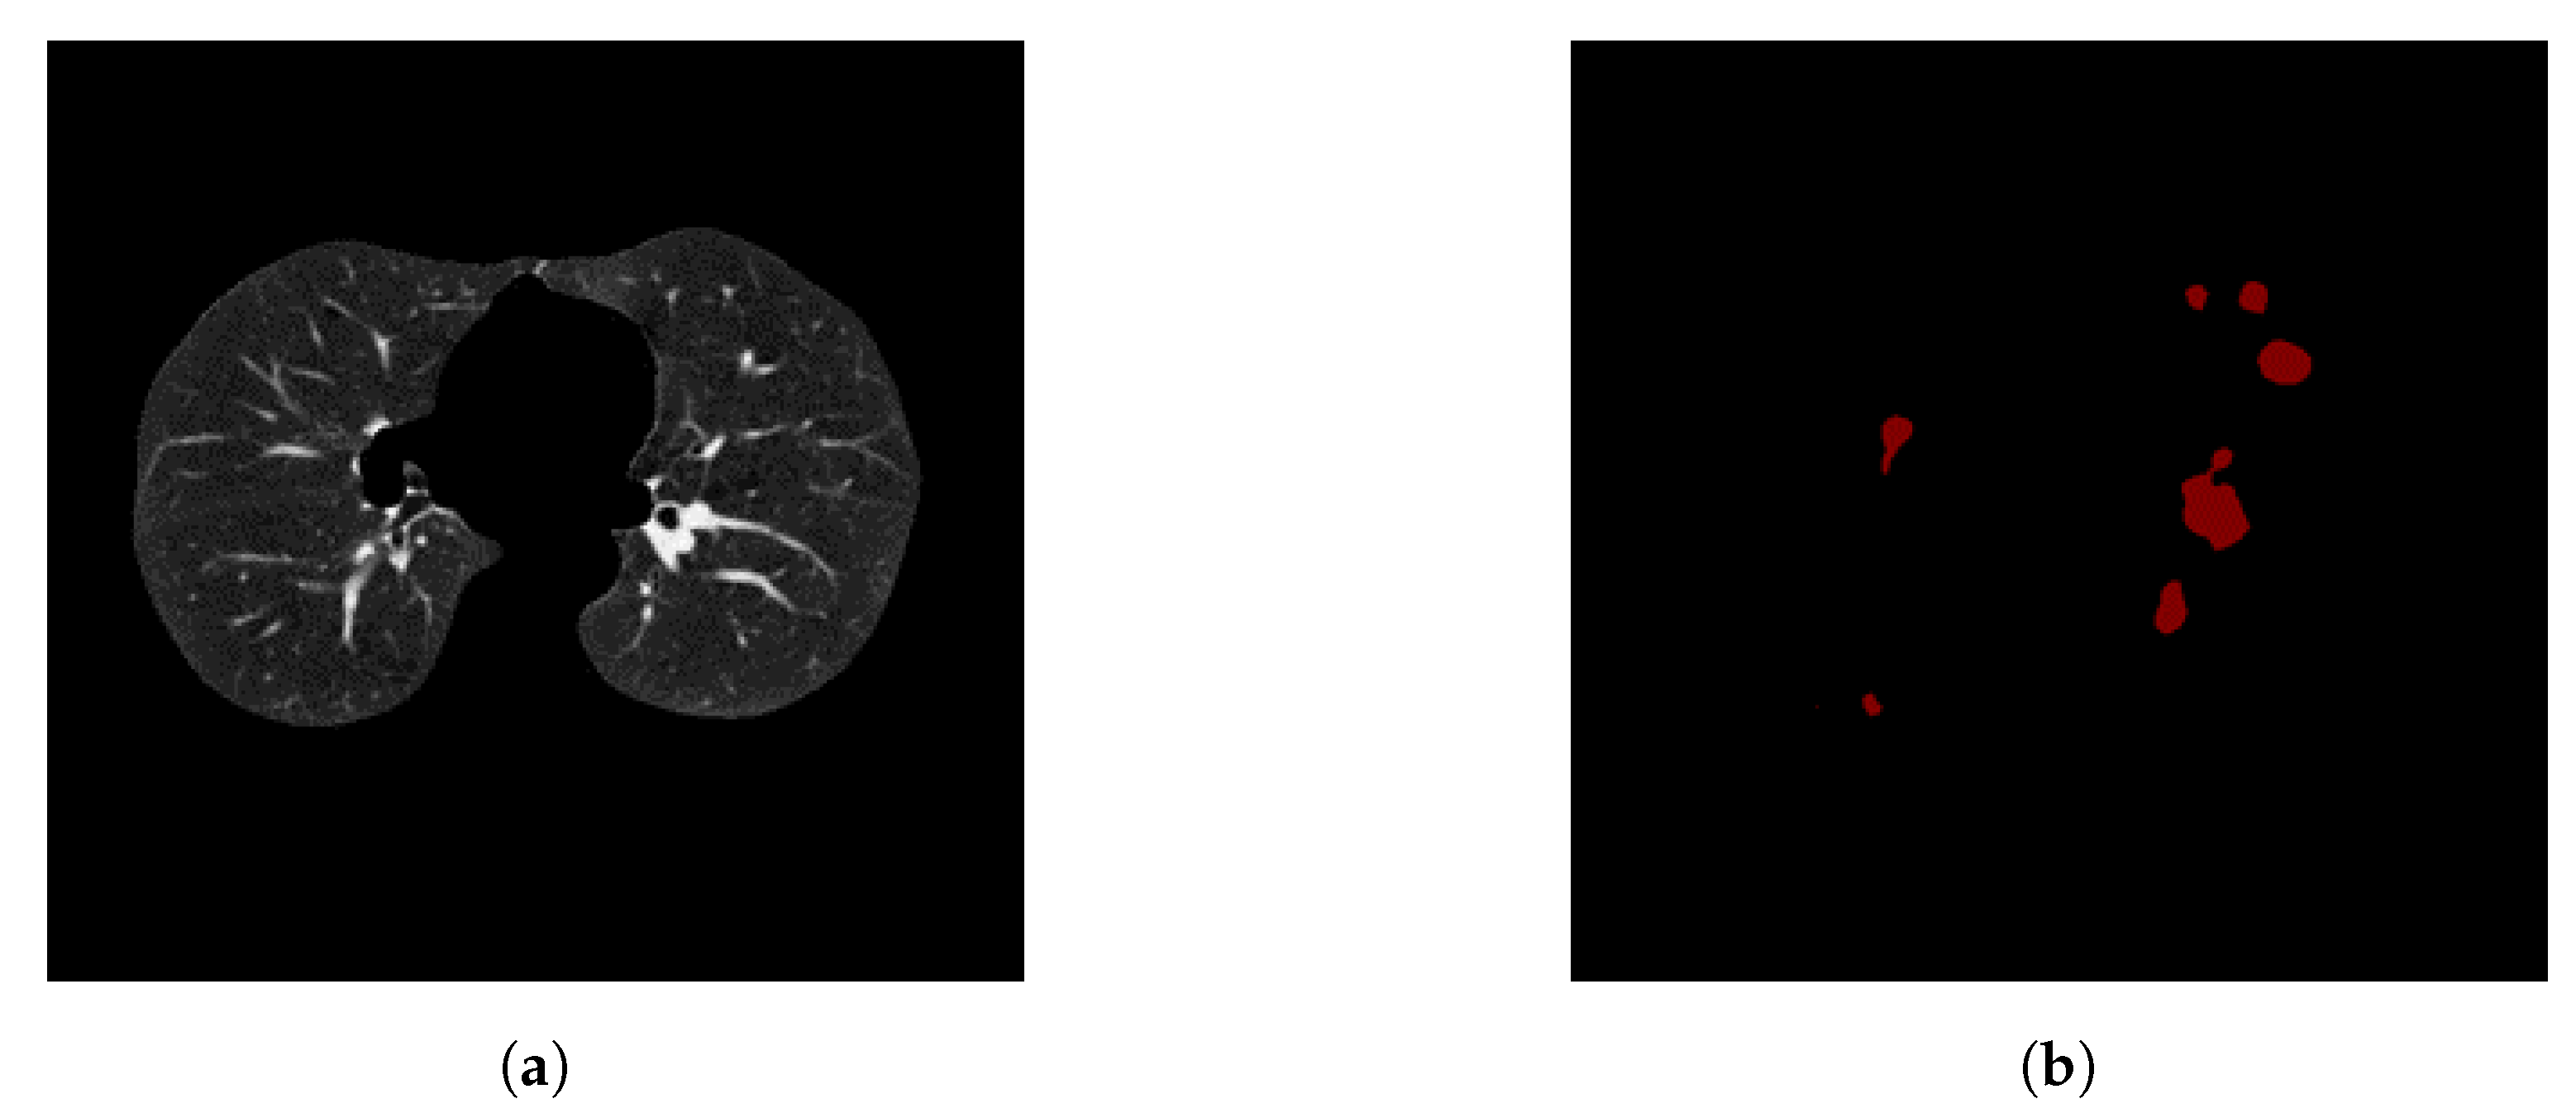

We utilize both datasets to train our system. A sample slice difference from one patient for both datasets is shown in Figure 3.

Figure 3. A sample slice from both Kaggle and LUNA datasets, showing a cross section of a patient chest cavity. Figure 3a shows a LUNA slice with an annotated nodule. Figure 3b shows that no annotations are given about nodule positions or sizes for Kaggle dataset.